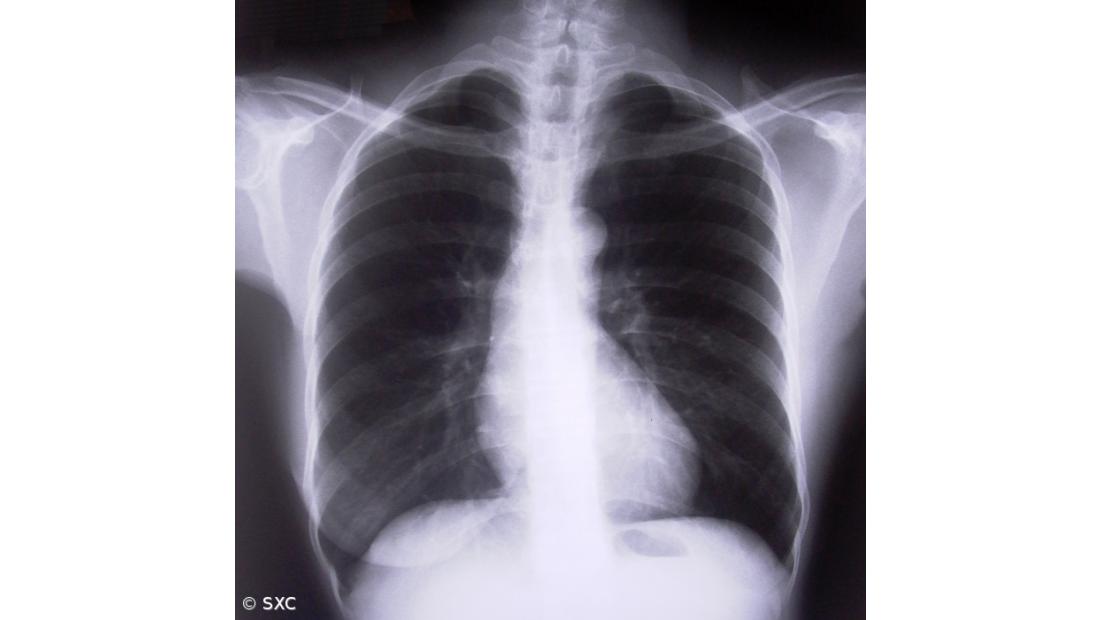

As doenças respiratórias, excluindo o cancro do pulmão, são a terceira principal causa de morte em Portugal e no mundo e a primeira causa de letalidade intra-hospitalar nacional.

No ano passado, da globalidade dos internamentos de causa respiratória (com exclusão das neoplasias respiratórias e dos internamentos por síndrome de apneia do sono), 65,3% corresponderam a internamentos por pneumonias (bacterianas ou virais), 13,5% por Doença Pulmonar Obstrutiva Crónica (DPOC), 5,7% por fibrose pulmonar e 4,3% por asma brônquica.